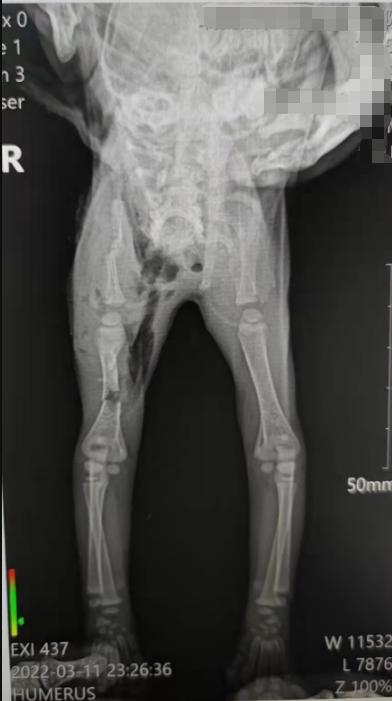

宠物基本情况: 宠物医生您好,一个月的小流浪猫猫被野猫咬伤,右肩胛骨伤口处有牙咬的洞,右手臂骨折了(图2),现在伤口化脓发炎,医生说白细胞少,小爪子黑了。真的不想他被截肢,他太小了,太受苦,求问医生这种伤口化脓应该怎么办啊,伤口化脓发炎应该怎么处理,怎么才能治好他的手,救救他!!!患病时长:四天;用药状况:目前在清洗伤口,想请问医生这种情况要包扎吗?

宠物医生回复: 家长您好,感谢您对友阳宠医的信任!您好,感谢您的耐心等待。 目前通过血常规发现炎症并且有贫血的情况。X光发现骨折,并且肌肉里面有气体,说明里面是有空腔的。

铲屎官问: 好的医生,小猫一直在治疗中的,没有着急给它做截肢手术。 请问现在这个情况,后面应该如何判断小猫伤口好不了必须截肢?医生,小猫一直在活动,请问需不需要固定他的手减少损伤之类的?动的时候可能会有摩擦还想问一下您小猫右手有腐败的气味的原因,因为医院医生可能是因为有腐败气味的原因才建议截肢的。